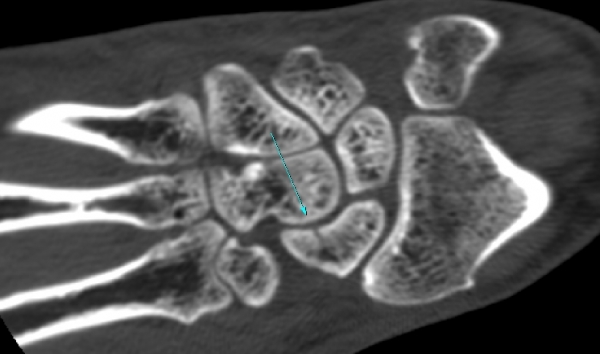

¼Õ¸ñ ÀåÃø ÁÖ»ó°ñ Á¾´Ü¸é °Ë»ç¿¡¼ ¹Ì¼¼ÇÑ ÁÖ»ó°ñ ÇÇÁú°ñ ¿¬¼Ó¼º ¼Ò½Ç(loss of cortical bone continuity)ÀÌ °üÂûµÊ(»çÁø 1, 2).

CT °Ë»ç